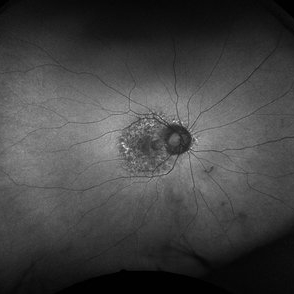

PPS FAF OD

Apr 10 2023 by Gordon Crabtree, MD

Right fundus autofluorescence of a woman on PPS for 15 years

Imaging device: Optos

Condition/keywords: macula, macula lesion, macular degeneration, pentosan sulfate